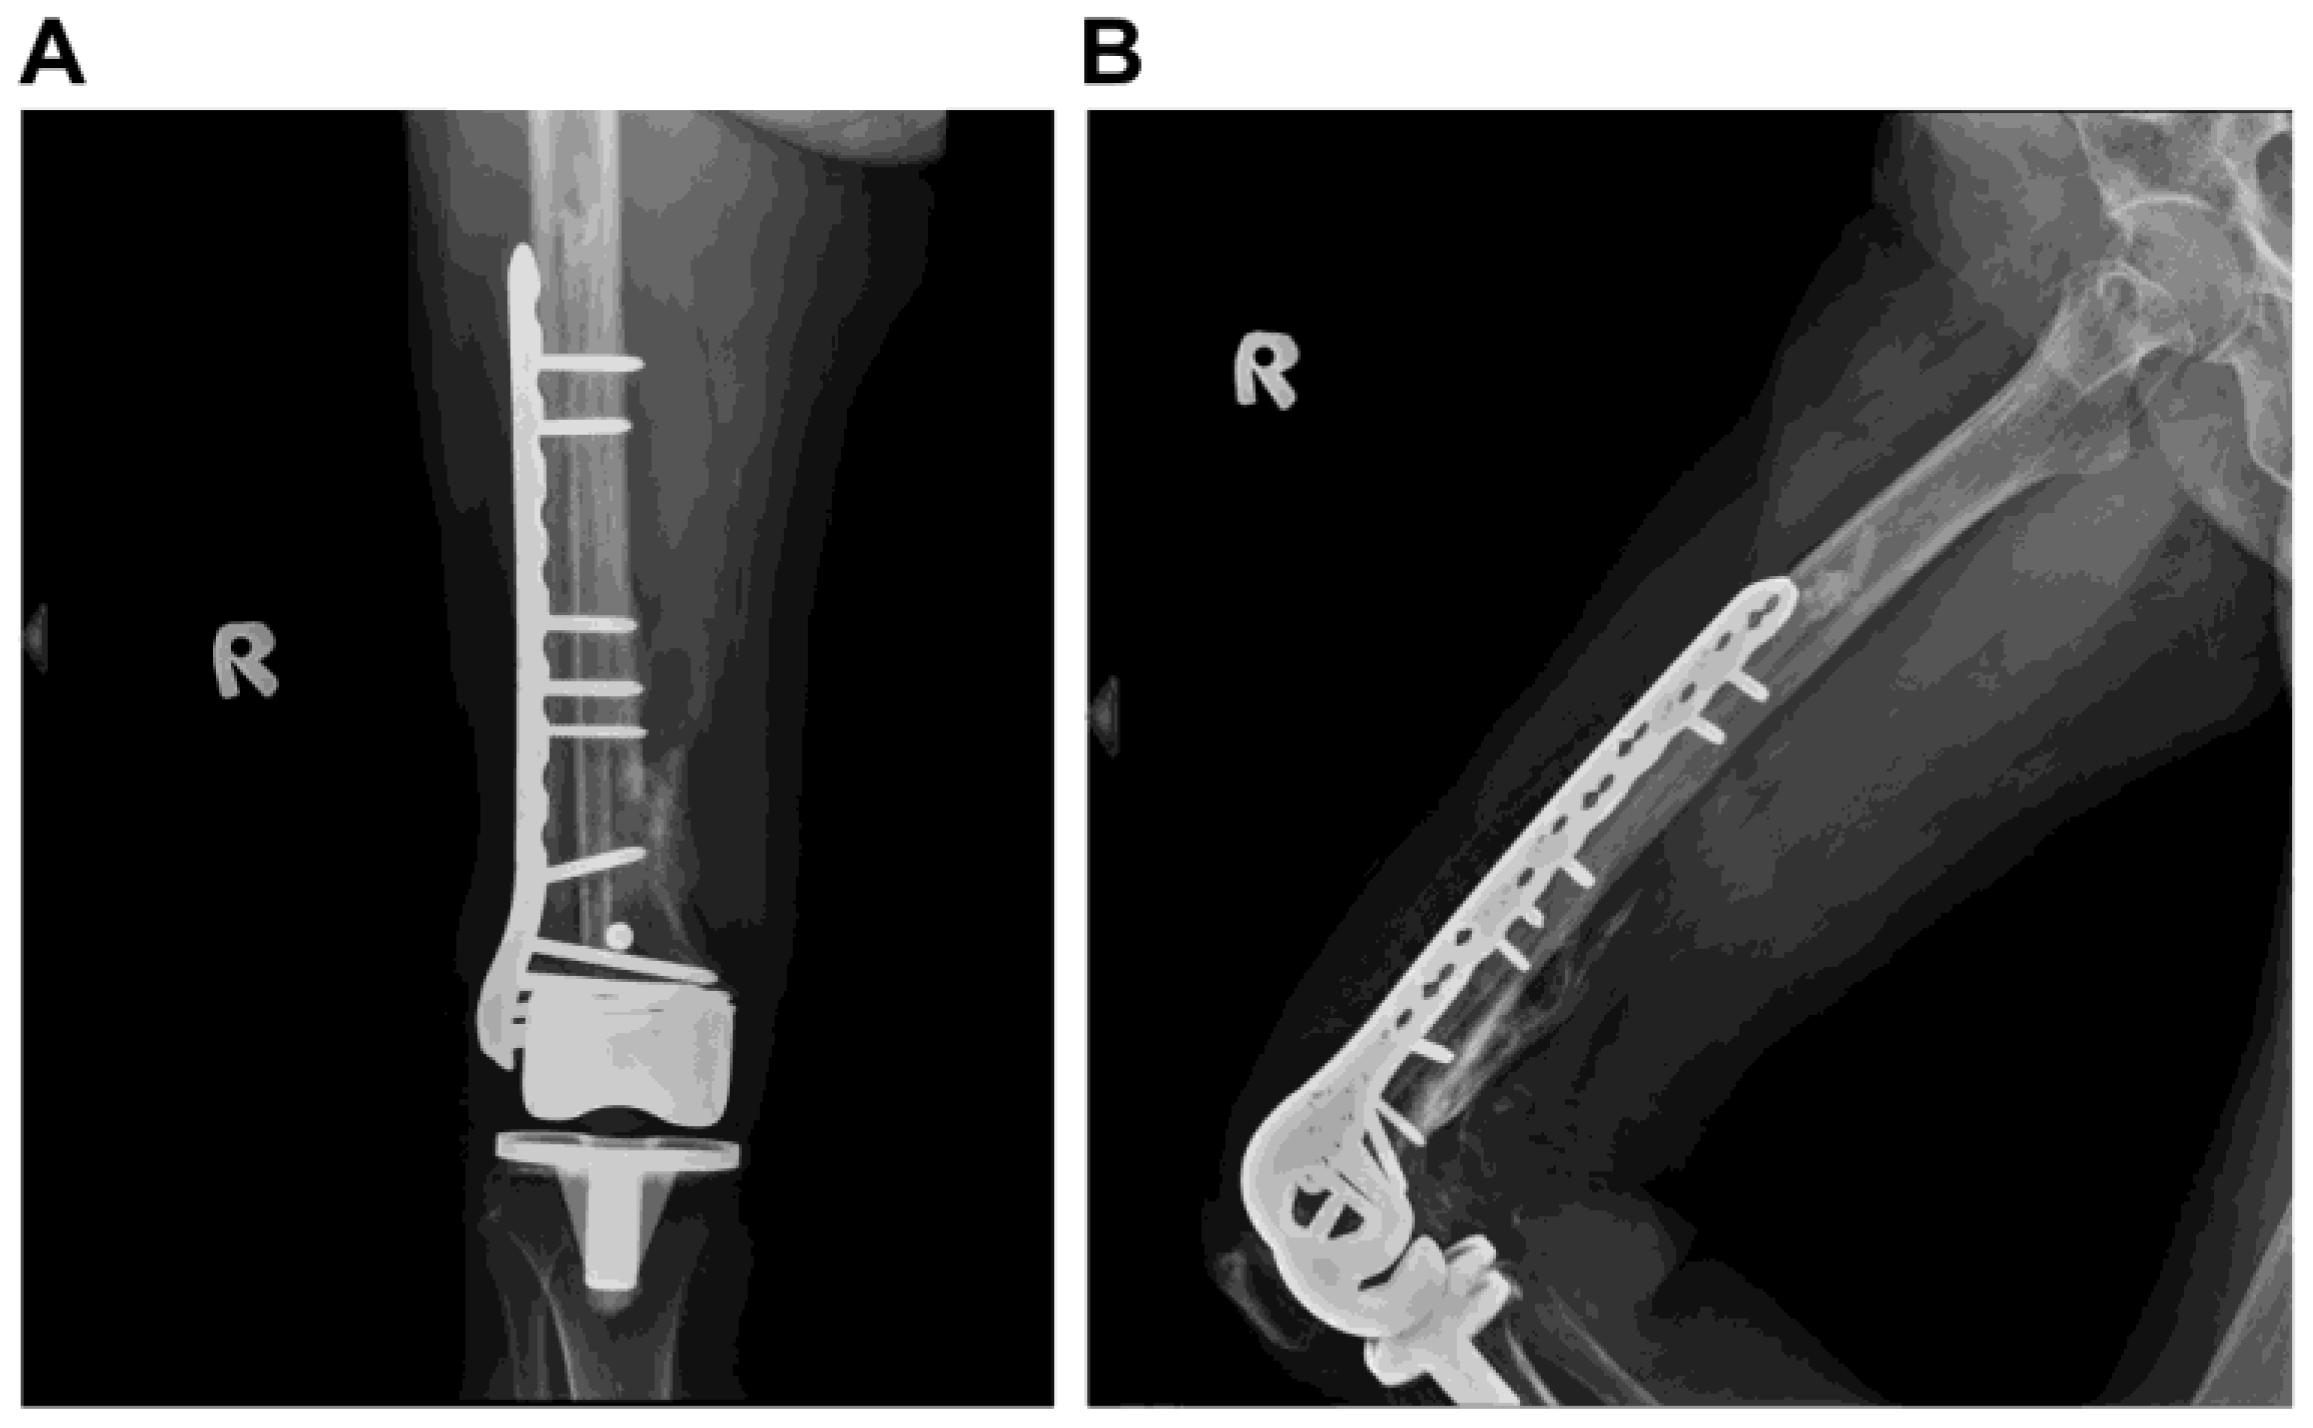

Successful Plate Fixation with Long Intramedullary Fibula Bone Graft for Periprosthetic Femur Fracture: A Case Report

2. Case Report